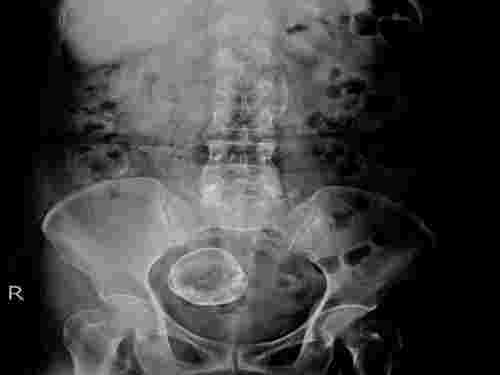

ซึ่งมีแพทย์เฉพาะทางด้านสูตินรีเวชกรรมและมะเร็งนารีเวช ผลตรวจออกมาว่าไม่ใช่มะเร็ง แต่ก้อนเนื้องอกมดลูกมีขนาดใหญ่ถึง 33 เซนติเมตร เทียบเท่าเด็กใกล้คลอด ก้อนเนื้อทับท่อไต ทำให้ปัสสาวะบ่อย ทับลำไส้ ทำให้กินได้น้อย จุกอืด ประกอบกับเลือดไหลไม่หยุด ส่งผลทำให้อ่อนเพลีย ความดันขึ้น จนเกือบจะเป็นลม

ไมโอมา หรือเนื้องอกมดลูก เป็นเนื้องอกชนิดไม่ร้ายที่พบบ่อยในผู้หญิงวัยเจริญพันธุ์ เนื้องอกนี้เกิดจากเซลล์กล้ามเนื้อเรียบของมดลูก มักมีลักษณะเป็นก้อนกลม แข็ง คล้ายยาง โดยขนาดของเนื้องอกมดลูก มีขนาดที่แตกต่างกันออกไป ตั้งแต่เล็กเท่าเมล็ดถั่วลันเตา ไปจนถึงใหญ่เท่าลูกเกรปฟรุต หรือมากกว่า ผู้หญิงบางคนอาจมีเนื้องอกหลายก้อนพร้อมกัน โดยไม่รู้ตัวเลย